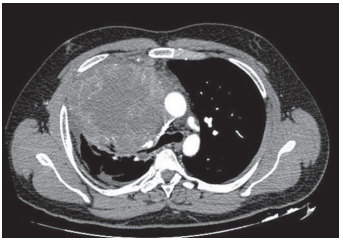

Um homem tabagista (cem anos‑maço) foi internado por perda de peso, baqueteamento digital, tosse seca e hemoptise. O quadro iniciou‑se há três meses, com piora recente. Realizou a tomografia de tórax mostrada a seguir.

Com base nessa situação hipotética e considerando a tomografia de tórax acima, assinale a alternativa que apresenta as alterações mais compatíveis com o exame físico esperado.